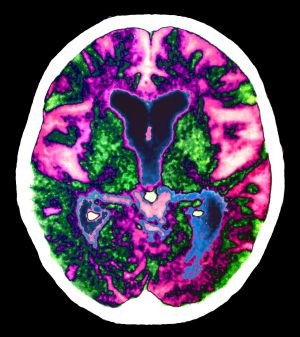

| Cerebro con Alzheimer. |

En concreto, el producto, llamado florbetapir, es radiactivo, y está diseñado para unirse a las proteínas beta-amiloides características de la enfermedad, que sería visible mediante PET (tomografía por emisión de positrones). Estas proteínas forman placas en las personas con Alzheimer, por lo que su detección puede servir para ver si empiezan a acumularse, y su evolución.